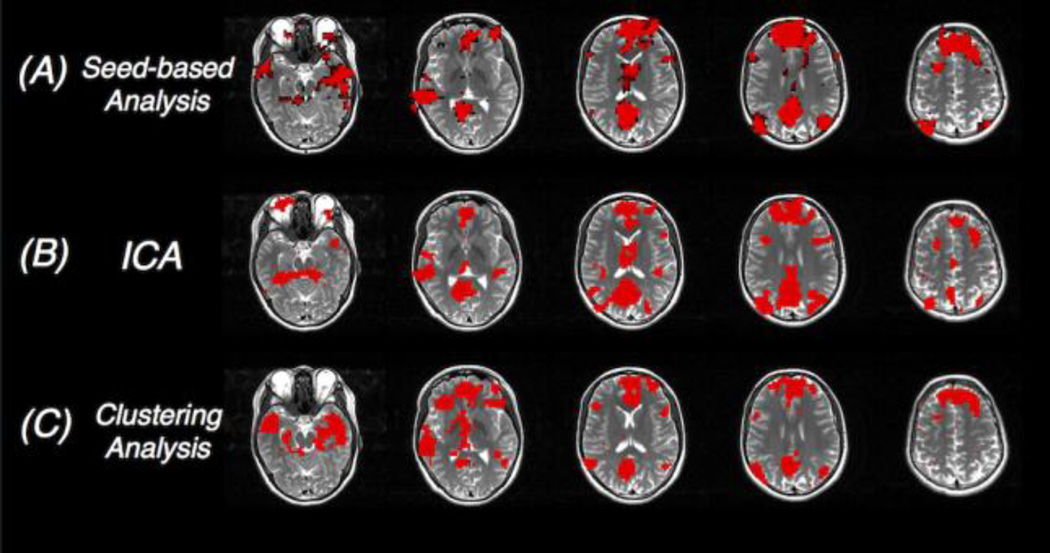

Figure 7.

Network patterns of the default mode network (a special resting state network) generated by different analyses approaches (red overlays). Results from the seed-based correlation analysis and ICA are thresholded for display.

A second type of analysis enables the exploration of whole-brain functional connectivity configuration without prior selections of network seeds using data-driven or model-free methods. Among all these model-free approaches, i.e., approaches without prior assumptions, independent component analysis (ICA) is the most frequently employed in task-free fMRI studies (see Figs. 6C and 7B) (McKeown and Sejnowski 1998, Calhoun, Adali et al. 2001, van de Ven, Formisano et al. 2004, Beckmann, DeLuca et al. 2005, Smith, Fox et al. 2009, Beckmann 2012). Very briefly, ICA separates the whole brain voxels into additive subcomponents by assuming that the subcomponents are non-Gaussian and they are statistically independent from each other. The spatial patterns of the obtained independent components (ICs) resemble those network patterns resolved by seed-based analysis (Greicius, Srivastava et al. 2004), and are consistent across different studies or subjects (Damoiseaux, Rombouts et al. 2006). Besides, ICA is able to identify certain non-neural sources of variability, such as motion or physiological noise, as separate subcomponents, and can therefore aid preprocessing (Liao, Krolik et al. 2005, Beckmann 2012). Major shortcomings of this approach include: (1) ICs correspond to more complicated representation of the raw fMRI data than seed-based functional connectivity maps, making it difficult to interpret group differences in clinical or neuropsychiatric applications; (2) the resolved ICs and their spatial patterns vary as a function of the number of subcomponents specified by the user; and (3) the classification of components into noise or signal is subject to user-induced interpretation bias.

In addition to ICA, several other model-free approaches have been proposed to characterize the functional connectivity patterns in task-free states. For instance, principal component analysis (PCA) projects the raw fMRI data into orthogonal spaces – principal components (PCs), and only focuses on the space spanned by the leading few PCs (i.e., PCs explaining the most variance of the original dataset) (Friston, Frith et al. 1993). A number of clustering techniques (Fig. 7C), such as hierarchical clustering (Cordes, Haughton et al. 2002), Normalized-cut (van den Heuvel, Mandl et al. 2008), Laplacian based clustering (Thirion, Dodel et al. 2006), fuzzy clustering (Chuang, Chiu et al. 1999), and spectral clustering (Craddock, James et al. 2012), have been applied to produce resting state networks as well. Clustering analysis attempts to parcellate the brain into distinct clusters such that intra-cluster similarity is higher than inter-cluster similarity. Naturally, voxels belonging to the same functional network (with strong temporal synchrony) will fall within the same cluster, if the cluster number is properly chosen.